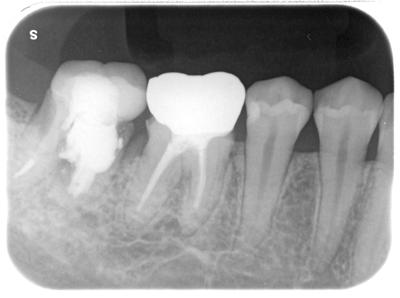

歯内療法専門医の治療を受けたものの、1年足らずで歯肉が腫れ、痛みが出て当院来院。

術前

パーフォレーションリペアと称してMTAが用いられているが、本来この歯は保存不可能と判断すべきであり、明らかな診断ミス。

MTAも歯根を大きく逸脱し、もはやリペアと言えるような状態ではない。

遠心根はボロボロ。

手前の6┓歯牙も大きなカリエスあるのだが、この部分は全く処置されておらず、問題の指摘もなかったそうである。